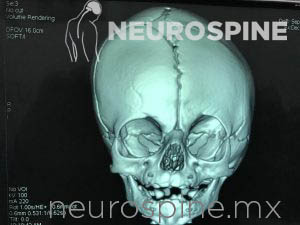

Malformaciones:

Malformaciones Craneales: Craneosinostosis